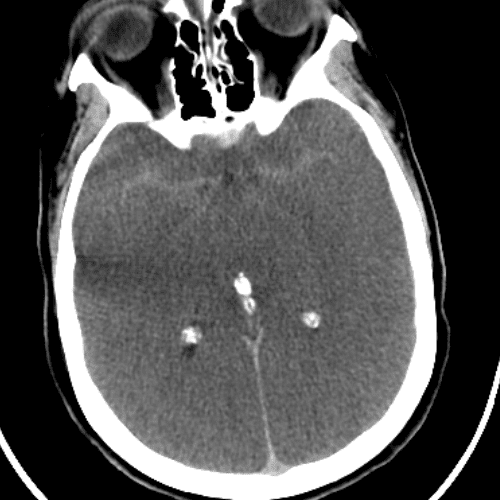

Choroid Plexus in Foramina of Luschka

Case 11